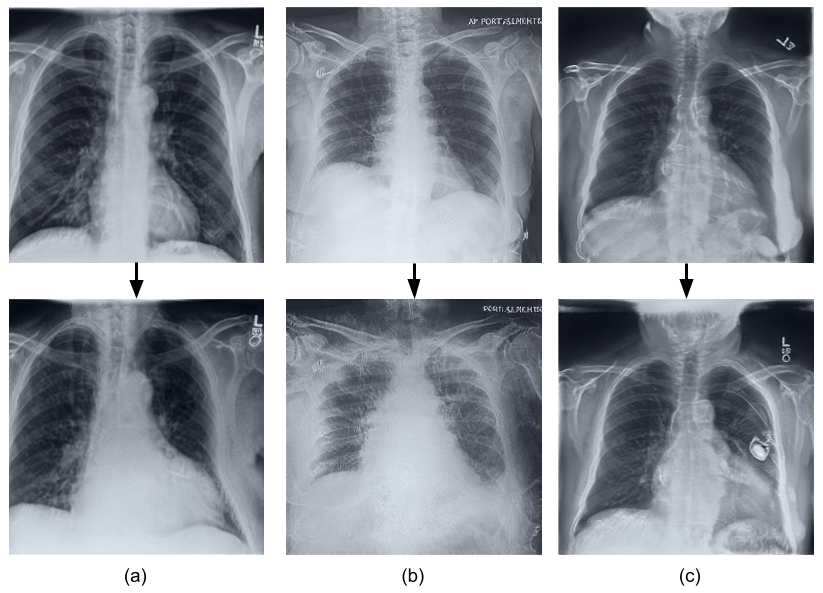

Deep learning models used in medical image analysis are prone to raising reliability concerns due to their black-box nature. To shed light on these black-box models, previous works predominantly focus on identifying the contribution of input features to the diagnosis, i.e., feature attribution. In this work, we explore counterfactual explanations to identify what patterns the models rely on for diagnosis. Specifically, we investigate the effect of changing features within chest X-rays on the classifier's output to understand its decision mechanism. We leverage a StyleGAN-based approach (StyleEx) to create counterfactual explanations for chest X-rays by manipulating specific latent directions in their latent space. In addition, we propose EigenFind to significantly reduce the computation time of generated explanations. We clinically evaluate the relevancy of our counterfactual explanations with the help of radiologists. Our code is publicly available.